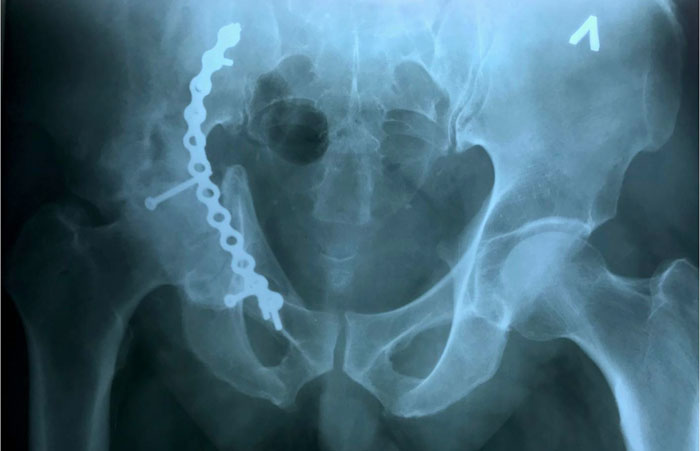

Травматологи первой горбольницы провели остеосинтез, зафиксировали кости таза с помощью специальной пластины из медицинского сплава. Такой «каркас» был создан для того, чтобы в будущем провести операцию по протезированию тазобедренного сустава. Врачам уже тогда было понятно, что в недалеком будущем он подвергнется дегенеративным изменениям и его функция не будет полноценной.

На снимке врачи увидели, что вертлужная впадина имеет нестандартную форму и размер, а головка сустава за это время полностью разрушилась.

«Для восстановления функции поврежденного сустава необходимо было провести эндопротезирование сустава. Если стандартный бедренный компонент может быть установлен при имплантации сустава, то тазовый эндопротез имплантировать с сохранением вертлужной впадины было практически невозможно. Нам необходимо было заместить дефект вертлужной впадины и создать условия для имплантации стандартного тазового компонента», – рассказал заведующий травматологическим отделением ГКБ № 1, врач-травматолог, ортопед Александр Троценко.